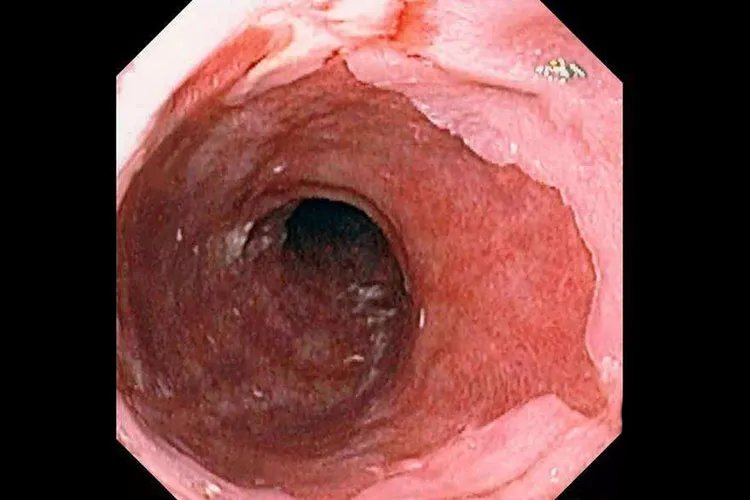

病因本病主要是由于食管下段括约肌压力低下,导致胃酸反流至食管,使食管暴露于胃酸时间过长而引起食管黏膜损害。主要与食管裂孔疝、妊娠、呕吐、呃逆、外科手术、以及各种器质性疾病,如食管下段及贲门部肿瘤、硬皮病和各种造成幽门梗阻的疾病有关。诊断本病可根据临床症状和内镜检查进行诊断。有明显的反流症状,可作出初步临床诊断,内镜下发现反流性食管炎表现即可诊断。此外,还可做X线钡餐造影、24小时食管pH监测、食管测压等检查,以判断反流情况和食管情况。治疗本病以非手术治疗为主,肥胖病人应减轻体重,避免持重、弯腰等动作,勿穿过紧衣裤。睡眠时抬高床头15cm,睡前6小时勿进食。药物治疗可应用制酸剂、促胃动力药物、抑酸剂、黏膜保护剂。因反流性食管炎形成的瘢痕性狭窄,对有吞咽困难症状者可行食管扩张术。此外,部分符合手术指征者可进行外科手术治疗。